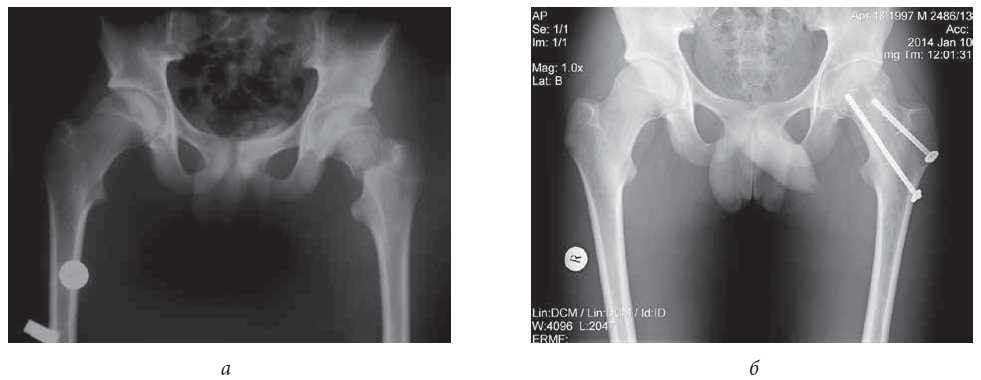

Patient M., aged 14 years, was transferred from the Central District Hospital of the city of S. with the diagnosis of closed basicervical fracture of the left femur neck with fragment displacement. The trauma had occurred 4 days prior as the result of a fall from height.

During the primary care hospitalization, the patient received conservative treatment including plaster immobilization and symptomatic therapy. On the hip joint radiographs in a frontal projection, a type III fracture according to Colonna classification was confirmed (Fig. 5, a). Surgical restorative treatment was performed. The complete consolidation of bone fragments at the fracture site was achieved after 7 months (Fig. 5, b).

Fig. 5. Patient M., 14 years old: a - X-ray of the hip joints before the operation in a direct projection: total disruption of the neck of the left femur in the cervical-neck area with displacement of the fragments; b - X-ray of the hip joints after closed reposition and fixation with cannulated screws in a straight projection: complete reposition with restoration of the neck-diaphysis angle